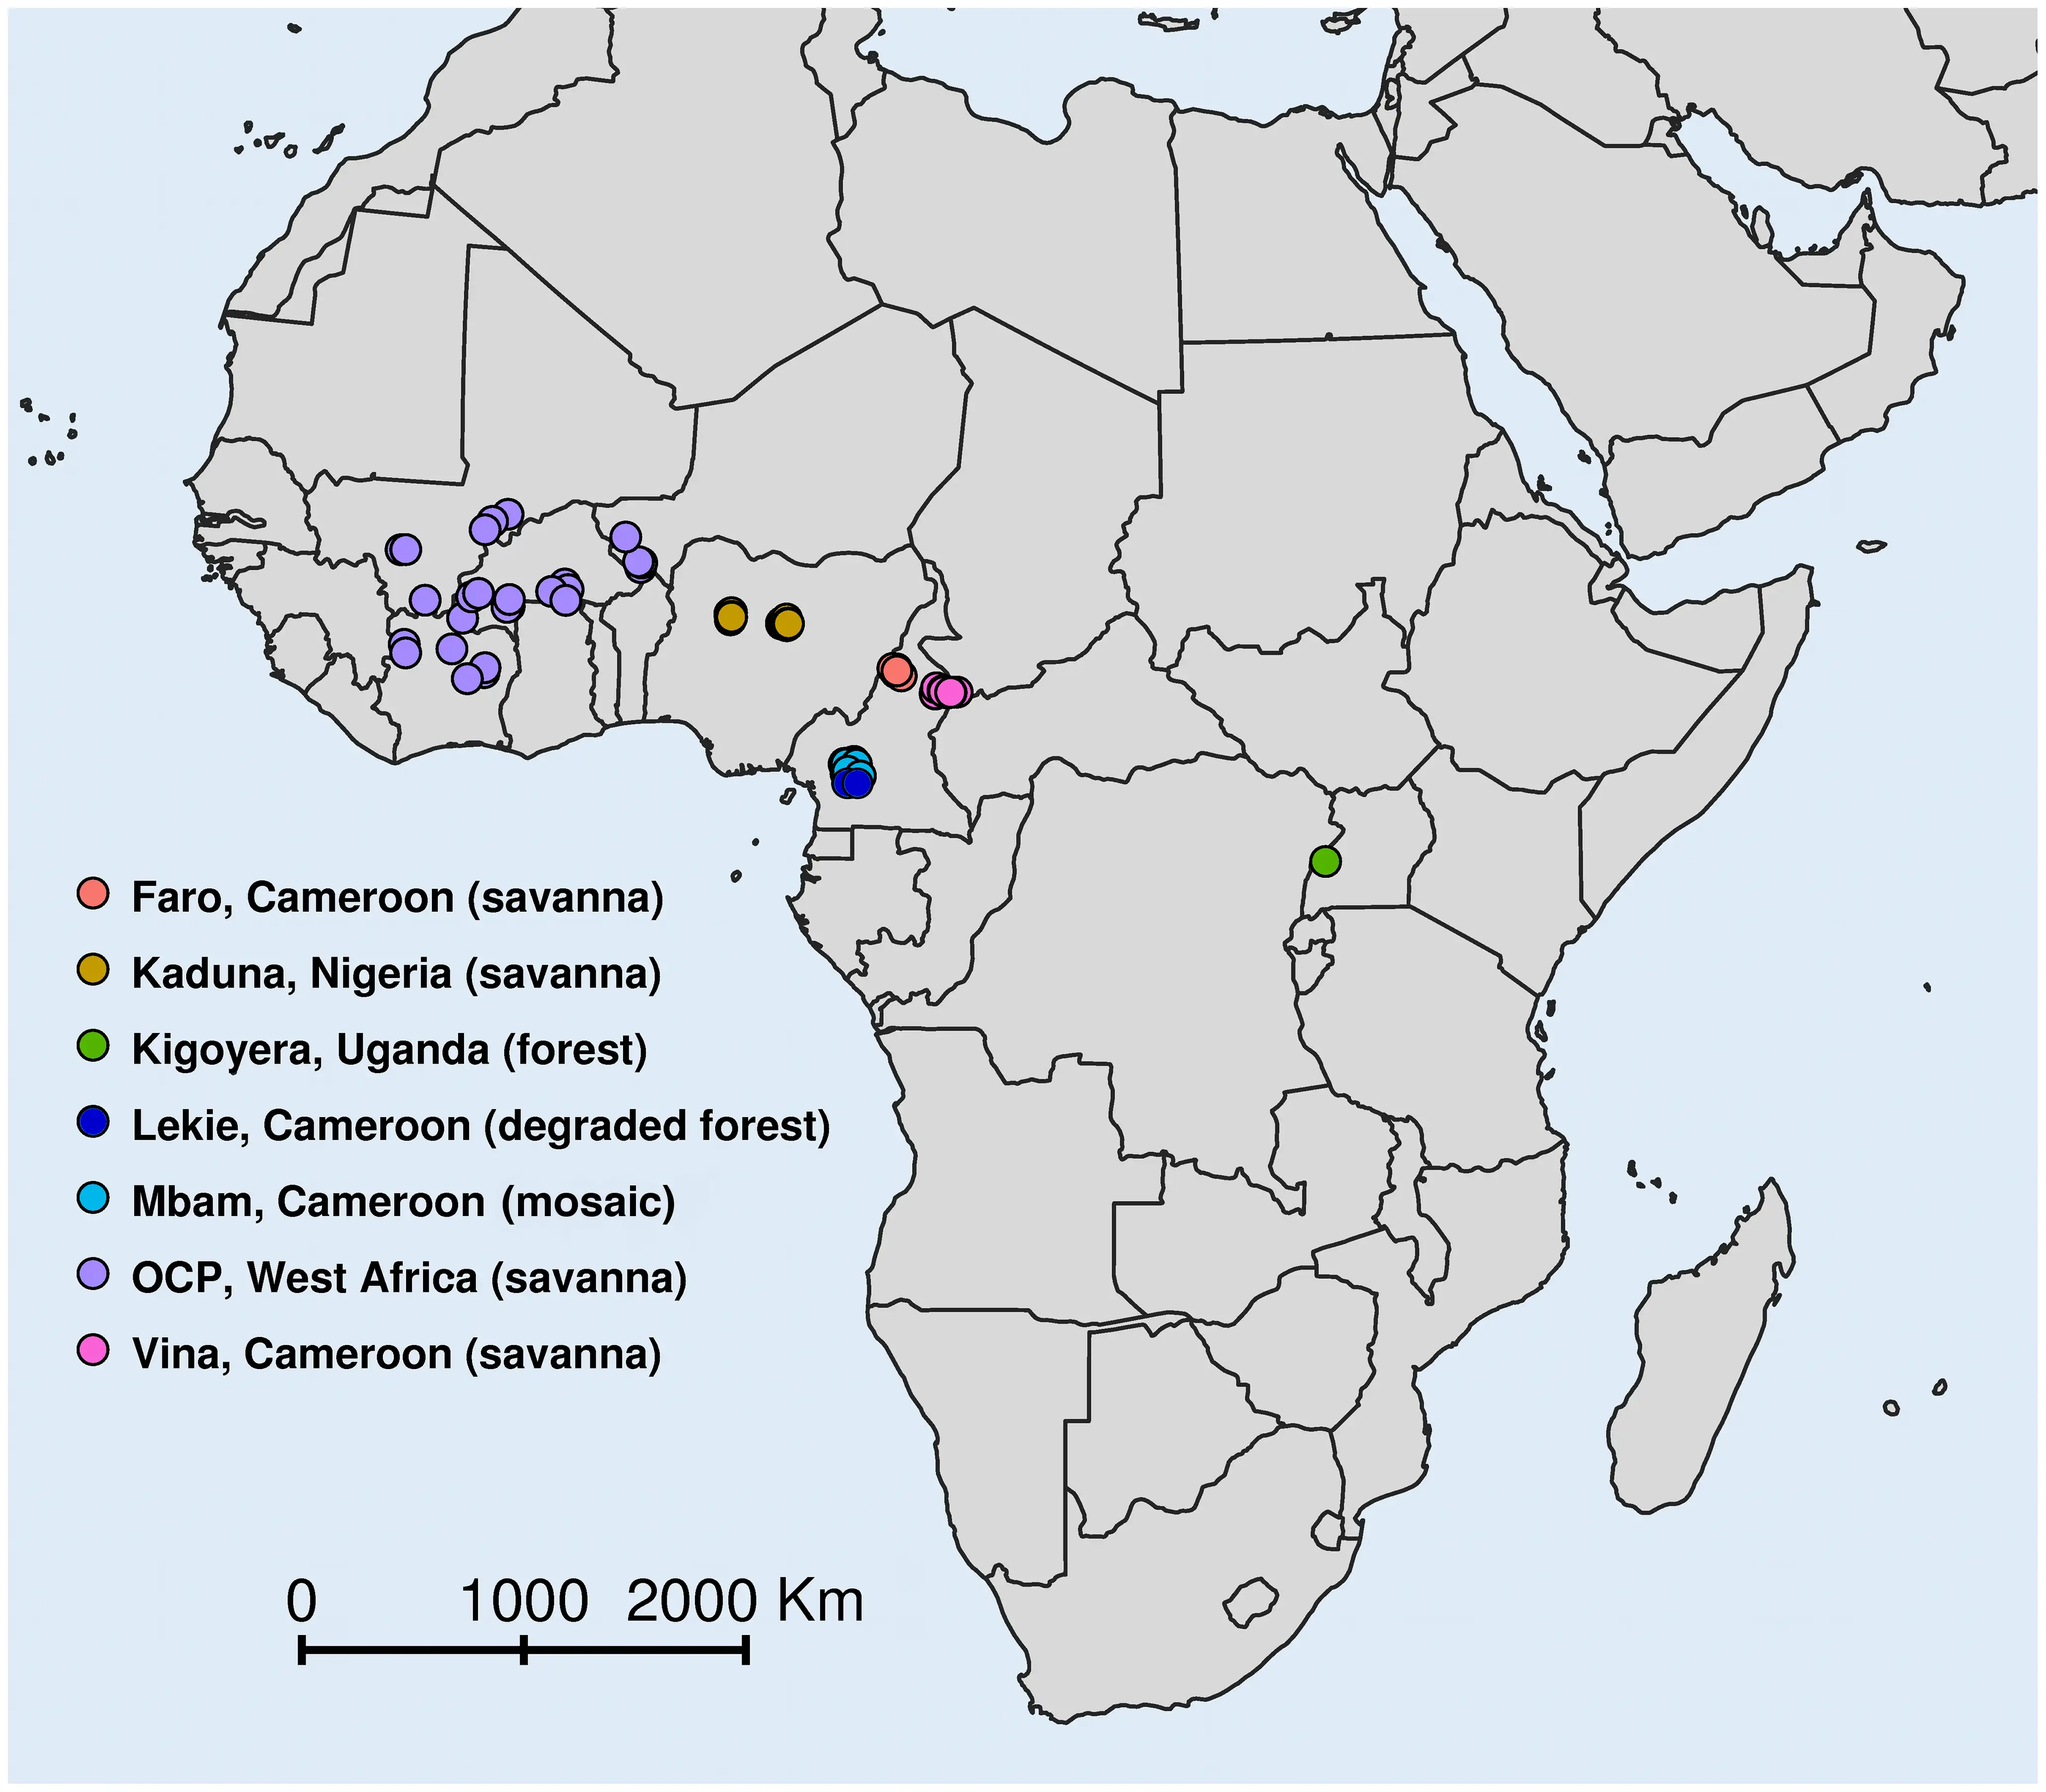

在非洲,传播河盲症的主要是 Simulium damnosus 复合种群的成员。这是一个包含数十个物种的复杂群体,不同物种在传播效率、叮咬习性和地理分布上各有不同。在西非的热带雨林地区,某些黑蝇物种更倾向于叮咬人类的下半身;而在稀树草原地区,其他物种则更喜欢叮咬躯干和上肢。这些行为差异直接影响着人体感染后微丝蚴在皮肤和眼部的分布模式,也解释了为什么不同地区的河盲症临床表现存在显著差异。

河盲症的眼部病理具有显著的地域差异。在西非的稀树草原地区,眼前段病变更为常见,失明率更高;而在热带雨林地区,后段眼球病变相对多见,但失明率较低。这种差异被认为与不同地区流行的盘尾丝虫株系的毒力差异有关。分子生物学研究证实,稀树草原株系和热带雨林株系在DNA序列上存在可检测的差异,而它们引起的角膜炎症反应也确实不同——稀树草原株系引发更严重的炎症反应。

盘尾丝虫病控制计划是世界上最大规模的热带病控制项目之一。它的诞生源于一个简单的观察:如果黑蝇需要湍急河流才能繁殖,那么通过在河流中投放杀幼虫剂杀死黑蝇幼虫,就可以阻断传播。这个计划覆盖了西非七个国家——贝宁、布基纳法索、科特迪瓦、加纳、马里、尼日尔和多哥,面积达65.4万平方公里,涉及约3000万人口。

结果令人振奋。在控制区域内,黑蝇密度下降了99%以上,传播几乎完全中断。曾经被废弃的肥沃河谷重新有人定居,农业生产力显著恢复。据估计,这项计划挽救了约60万人免于失明,为约1800万儿童提供了无河盲症的成长环境,并使约2500万公顷的废弃农田重新得到耕种。

然而,控制计划的成功并非一帆风顺。黑蝇的远距离飞行能力意味着来自控制区外的黑蝇可以重新引入疾病。为了应对这个问题,控制区域被逐步扩大,最终覆盖了11个国家。环境问题也曾引发担忧——大量杀虫剂进入河流生态系统,对鱼类和其他水生生物造成影响。这些问题促使研究者开发更环保的控制方法。